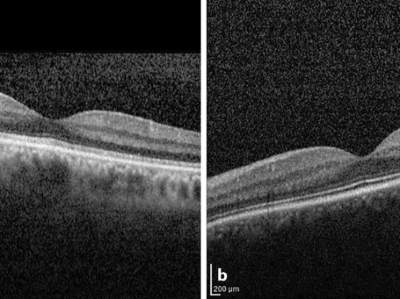

Bildnachweise